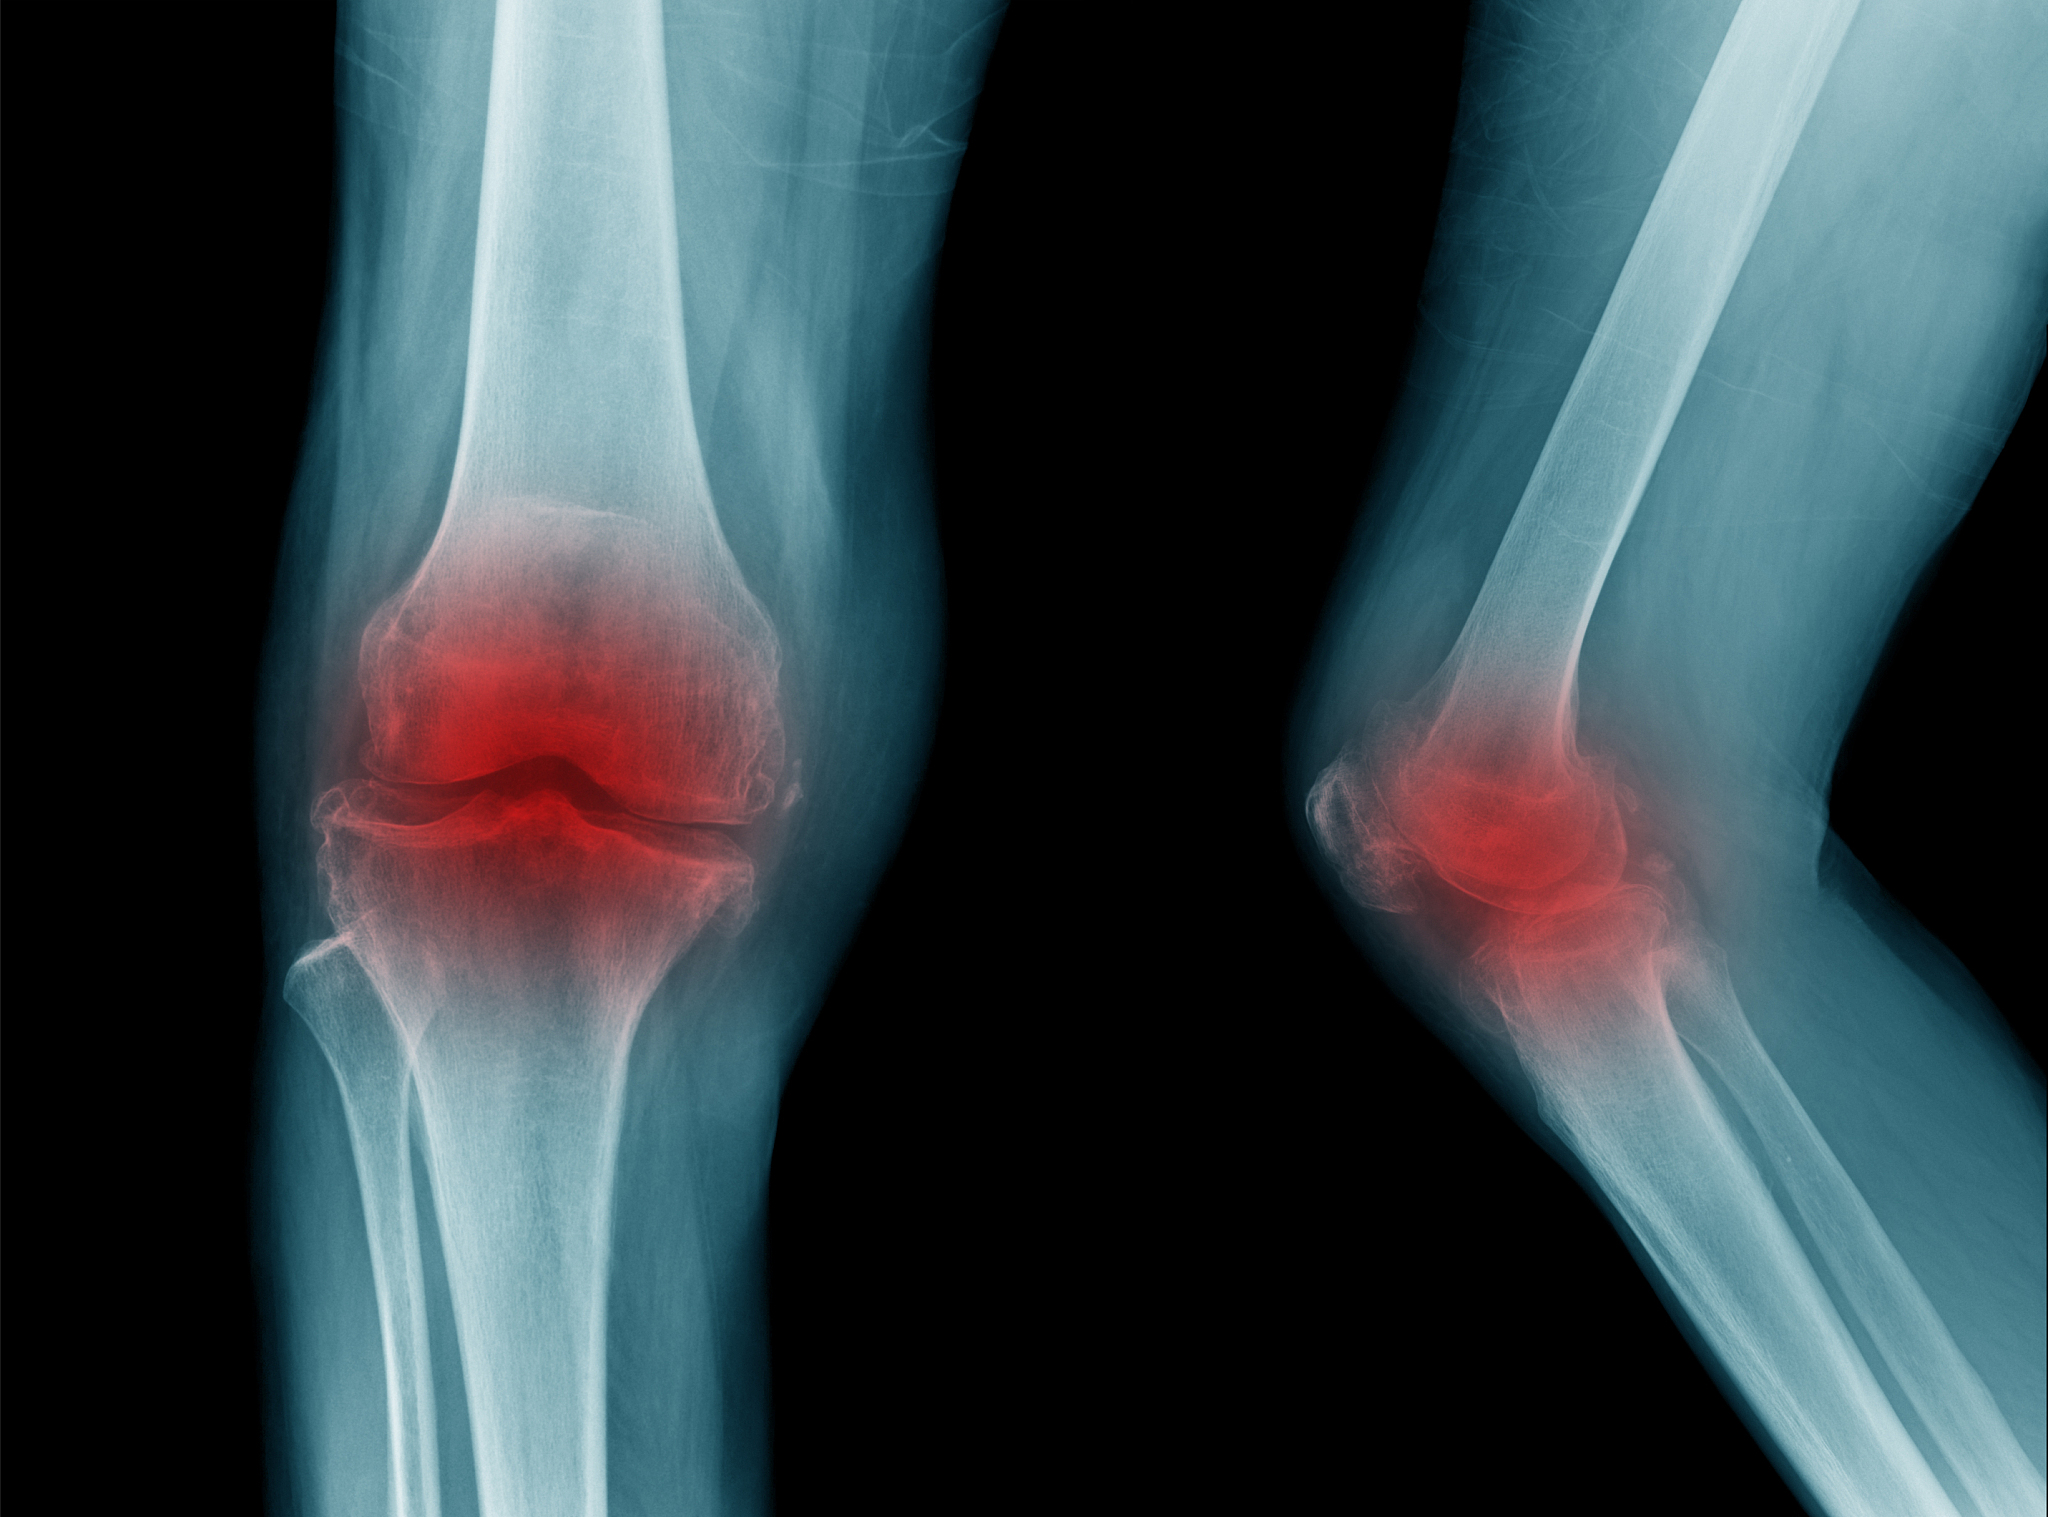

膝关节骨性关节炎是一种慢性炎症性疾病,主要影响膝关节。它通常是由于关节软骨的退化和破坏引起的,导致关节变形、疼痛和功能障碍。

膝关节骨性关节炎的症状包括膝关节疼痛、僵硬、肿胀和活动受限。疼痛通常会在活动后加重,而休息和睡眠时会减轻。随着疾病的进展,膝关节可能会变形,导致腿部畸形和行走困难。

膝关节骨性关节炎的风险因素包括年龄、肥胖、关节受伤、家族遗传、肌肉无力和关节过度使用。诊断通常通过病史、体格检查和影像学检查(如X射线或MRI)进行。